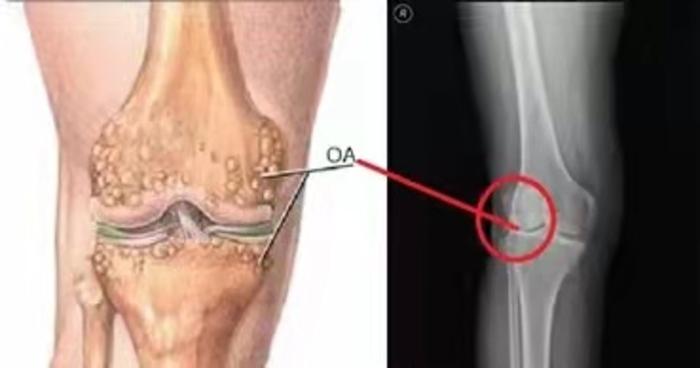

随着老龄化社会的步入,老年人口数的不断上升,骨关节炎(OA)也成为威胁中老年人群健康,致残中老年人群的主要因素之一。全球约有1.9亿OA患者,且人数不断增加,发病率随年龄递增,小于40岁为5%,60岁~75岁高于50%,大于75岁高达80%

膝关节骨性关节炎是OA的最常见类型,是一种慢性、无菌性、进行性侵犯关节的炎症,最终致关节疼痛,畸形和功能障碍,影响病人的活动能力和生活质量。资料表明60岁以上人群,几乎100% 有膝关节退变的组织学表现,60%80%可见OAX线征象,其中20%有疼痛和活动受限;国内的发病率高达8.3%

膝骨关节炎的诊断